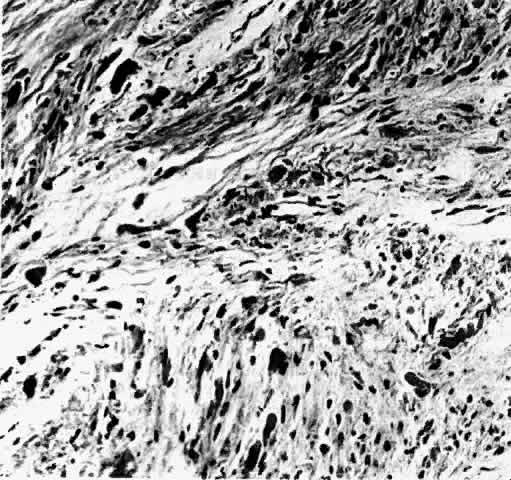

Gross examination of optic nerve gliomas usually reveals a smooth, fusiform, intradural enlargement of the optic nerve (Fig. 6). After extending through the optic canal in a dumbbell fashion, there may be extension to posterior structures.4 Most optic gliomas are classified as juvenile pilocytic astrocytomas and have a benign histologic appearance. Pilocytic refers to the spindle-shaped astrocytes with elongated nuclei that are often arranged in a parallel fashion (Fig. 7). Oligodendroglial cells may be scattered throughout the glioma. These tumors can contain carrot- or cigar-shaped eosinophilic astrocytic cytoplasmic inclusions known as Rosenthal fibers4 (Fig. 8). Microcystoid extracellular spaces containing acid mucopolysaccharide generated by mucin-producing astrocytes are often seen.85 Less common features can include capillary hyperplasia, mitotic figures, tissue necrosis with hemorrhage,86 and glial giant cells.4

Fig. 7. Photomicrograph of an optic nerve glioma, demonstrating a mixture of pilocytic astrocytes and some oligodendro-glial cells.

Fig. 8. Optic nerve glioma. The numerous carrot-shaped or cigar-shaped dark bodies are called Rosenthal fibers (Verhoeff's bodies). (H & E, × 176; Courtesy of Drs. Eggers, Jakobiec, and Jones)